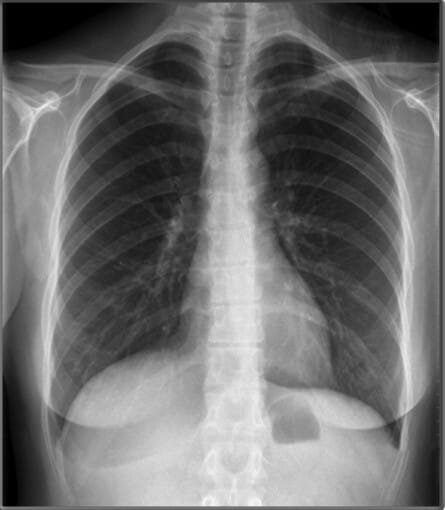

Chest PA view

PA (Posterior-anterior) – 방사선 (X선) 이 후방에서 전방으로 이동